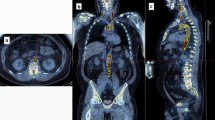

SUV was calculated using the operator-guided computer software PMOD (PMOD

Technologies LLC, Switzerland). CT and PET images for each participant were uploaded onto the software and manipulated to create regions of interest (ROIs) on each CT image slice. This was done by segmenting regions around the heart on each 3.75-mm thick coronal slice, moving anteriorly to posteriorly. These ROIs were then stacked to create 3D volumes of interest (VOIs). The VOIs encompassed only the vascular tissue of the heart—blood and the surrounding thoracic cavity were excluded by setting a threshold with a lower limit of – 50 HU (Fig. 1). The VOIs were generated using the CT images for structural clarity, then superimposed on the corresponding PET images. From here, average SUV (SUVmean) and maximum SUV (SUVmax) were calculated within each VOI.

Comparing patients to controls

Despite having similar HU values (0.88 HU lower among patients, CI − 3.05–1.30, P = 0.42), compared to matched controls, patients had higher SUVmean (0.09 g/mL higher among patients, CI 0.03—0.15, P = 0.01), but not SUVmax (0.04 g/mL lower among patients, CI − 1.06–0.98, P = 0.94; Fig. 2), which was quite noticeable visually (Fig. 3). Patients also had higher 10-year Framingham Risk Scores (2.45 higher among patients, CI 0.46–4.45, P = 0.02; Fig. 4). However, no differences were detected between patients and healthy controls on any calcium score measure (calcium mass, 58 mg lower among patients; CI − 481.93–365.93, P = 0.75; calcium volume, 65.71 mm lower among patients; CI − 458.34–326.91, P = 0.70; calcium score, 69 AU lower among patients; CI − 622.25–484.25, P = 0.77; Fig. 5).